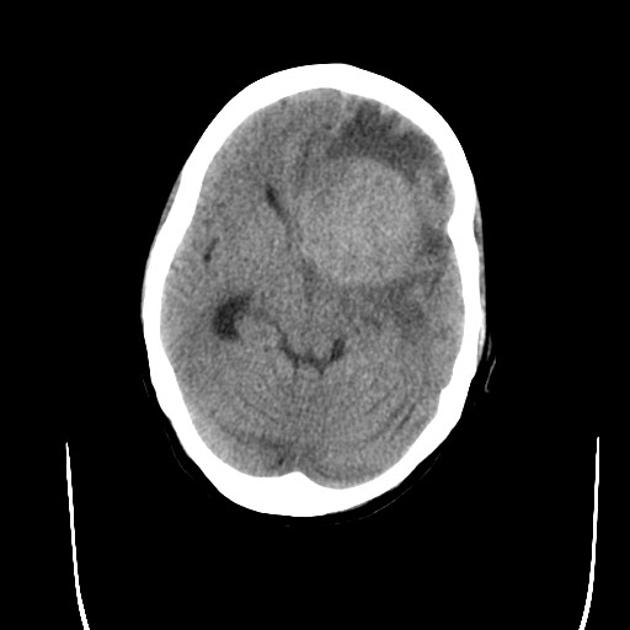

CT Imaging

CT images are hypointense. Hemorrhage is uncommon. Multiple lesions are more common in HIV+ patients.